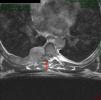

Clinical ObservationA 52-year-old man, with no medical history of interest, presented with a 6-month history of dorsal thoracic pain. As the patient's symptoms did not improve, it was decided to perform magnetic resonance imaging (MRI), following a normal chest radiograph. The diagnosis was costal hydatidosis with intraspinal extension (Fig. 1). Due to questions about the nature of this process, a thoracoabdominal computed tomography (CT) scan was requested, in which an 88mm×60mm×95mm right paravertebral mass was found. It was predominantly cystic with lobulated contours, extrapleural morphology and protruded through the right foramen between the sixth and seventh costal arches towards the spinal canal, extending paravertebrally from the fourth to the seventh right posterior costal arches, involving the extrapleural fat and extending towards the dorsal muscles through the intercostal spaces, with no costal involvement. As a result, the new suspected diagnosis was soft tissue sarcoma (Fig. 2). Fine needle aspiration was carried out (non-diagnostic). Given the intraspinal finding of the mass, it was decided to use a combined neurosurgical and thoracic approach.